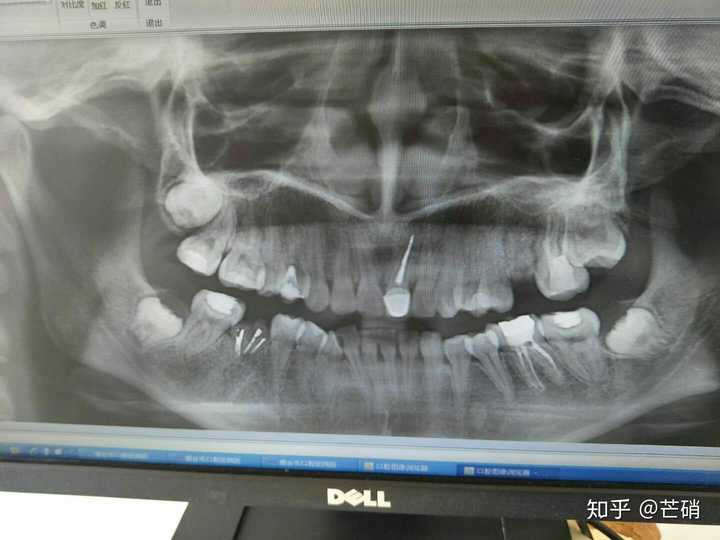

正常牙的牙片图片,正常健康的牙片图片

给大家欣赏一下我的牙牙

全景牙片图片